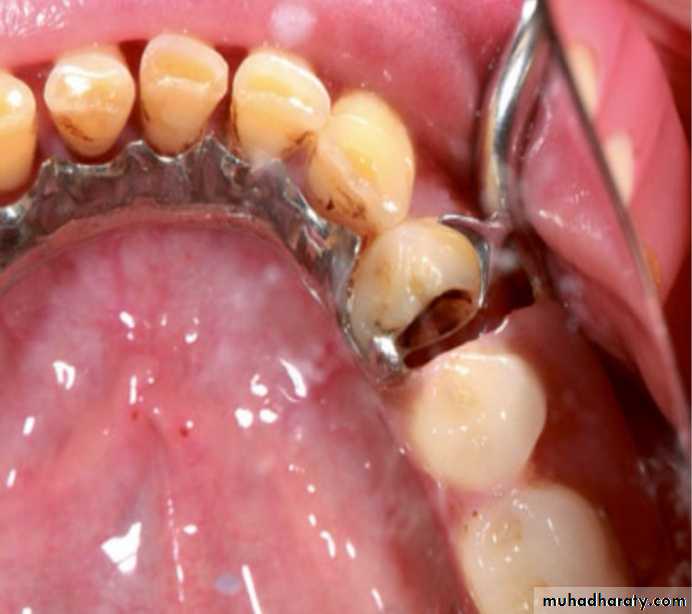

Clasps may not function properly in case of wear of the abutments due to caries, abrasion, or erosion on the facial or proximal surfaces or because of patient misuse.

The clasp assemblies may lose their retentive

properties due to caries of the abutment teeth

If this procedure has not been employed before, the clasps of the RPD are obliged to be loosened every time. If wear exists on the abutments, the nonfunctioning clasps may be changed to functioning by adding composite material to the teeth surfaces and bending the retentive arms into the deepened undercuts with pliers.